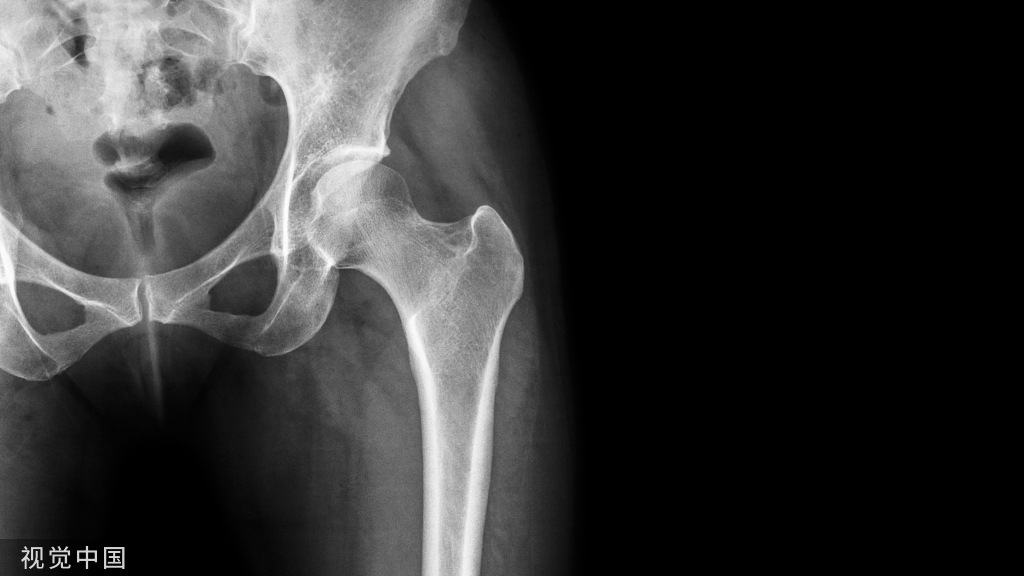

受伤时姿势如:滑倒时,手会不由自主地先着地,这时手臂易骨折;从自行车上摔下,侧身而臀部的髋骨先着地,则髋骨易骨折。